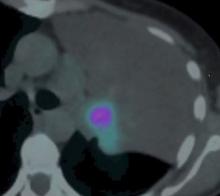

A 52-year-old female smoker was diagnosed with an 8 cm left upper lobe non-small cell carcinoma, with vascular and bronchial involvement. Flexible bronchoscopy confirmed that the orifice of the left upper bronchus was fully occluded by the tumor mass. The patient agreed to a left upper lobe resection through a left hemiclamshell approach.